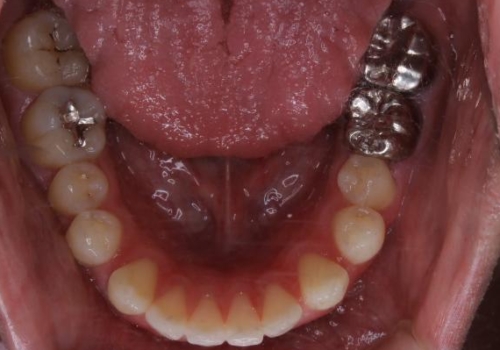

- 全体的に歯と歯の間に隙間があるのが気になるとのことで来院されました。インビザラインでの矯正治療をご希望されました。

隙間については、前歯と奥歯に多数あります。また、上下前歯は、外側に少し倒れているため隙間を閉じつつ、前歯を内側に引っ込めて並べることになりました。

インビザライン・ライトにて矯正治療を行うことになりました。